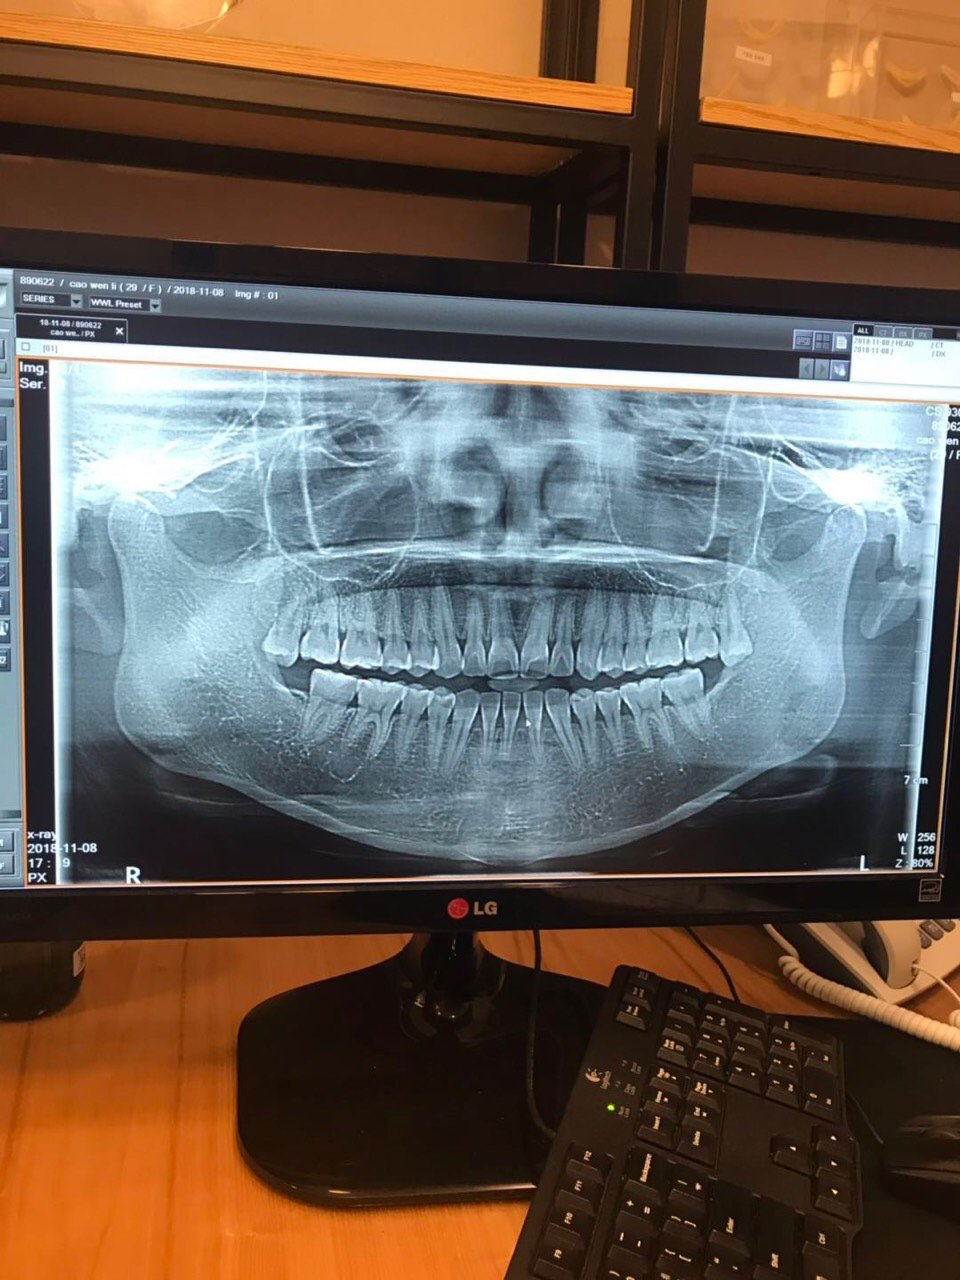

ct片子出来了,好宽的脸啊!

图片尺寸1080x1440

图片是我的ct,正面脸真的好大,想要修复下颌角.

图片尺寸570x760